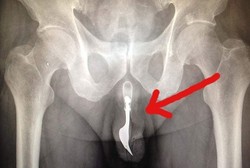

Helen dan James begitu khawatir dengan keadaan putranya yang berusia dua tahun, Ewan Delap. Sebab Ewan kesulitan bernapas dan mengalami mengi. Bergegas orang tuanya membawa Ewan ke rumah sakit. Saat pemeriksaan, ditemukan benjolan di tenggorokan Ewan yang ditengarai sebagai tumor.